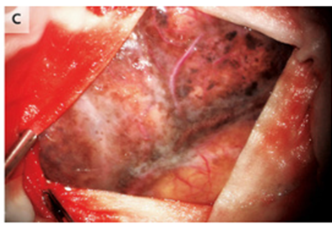

留置中、硬膜を切開した後、黒色化した髄膜が見られた。

髄膜の生検サンプルは悪性黒色腫と一致した。